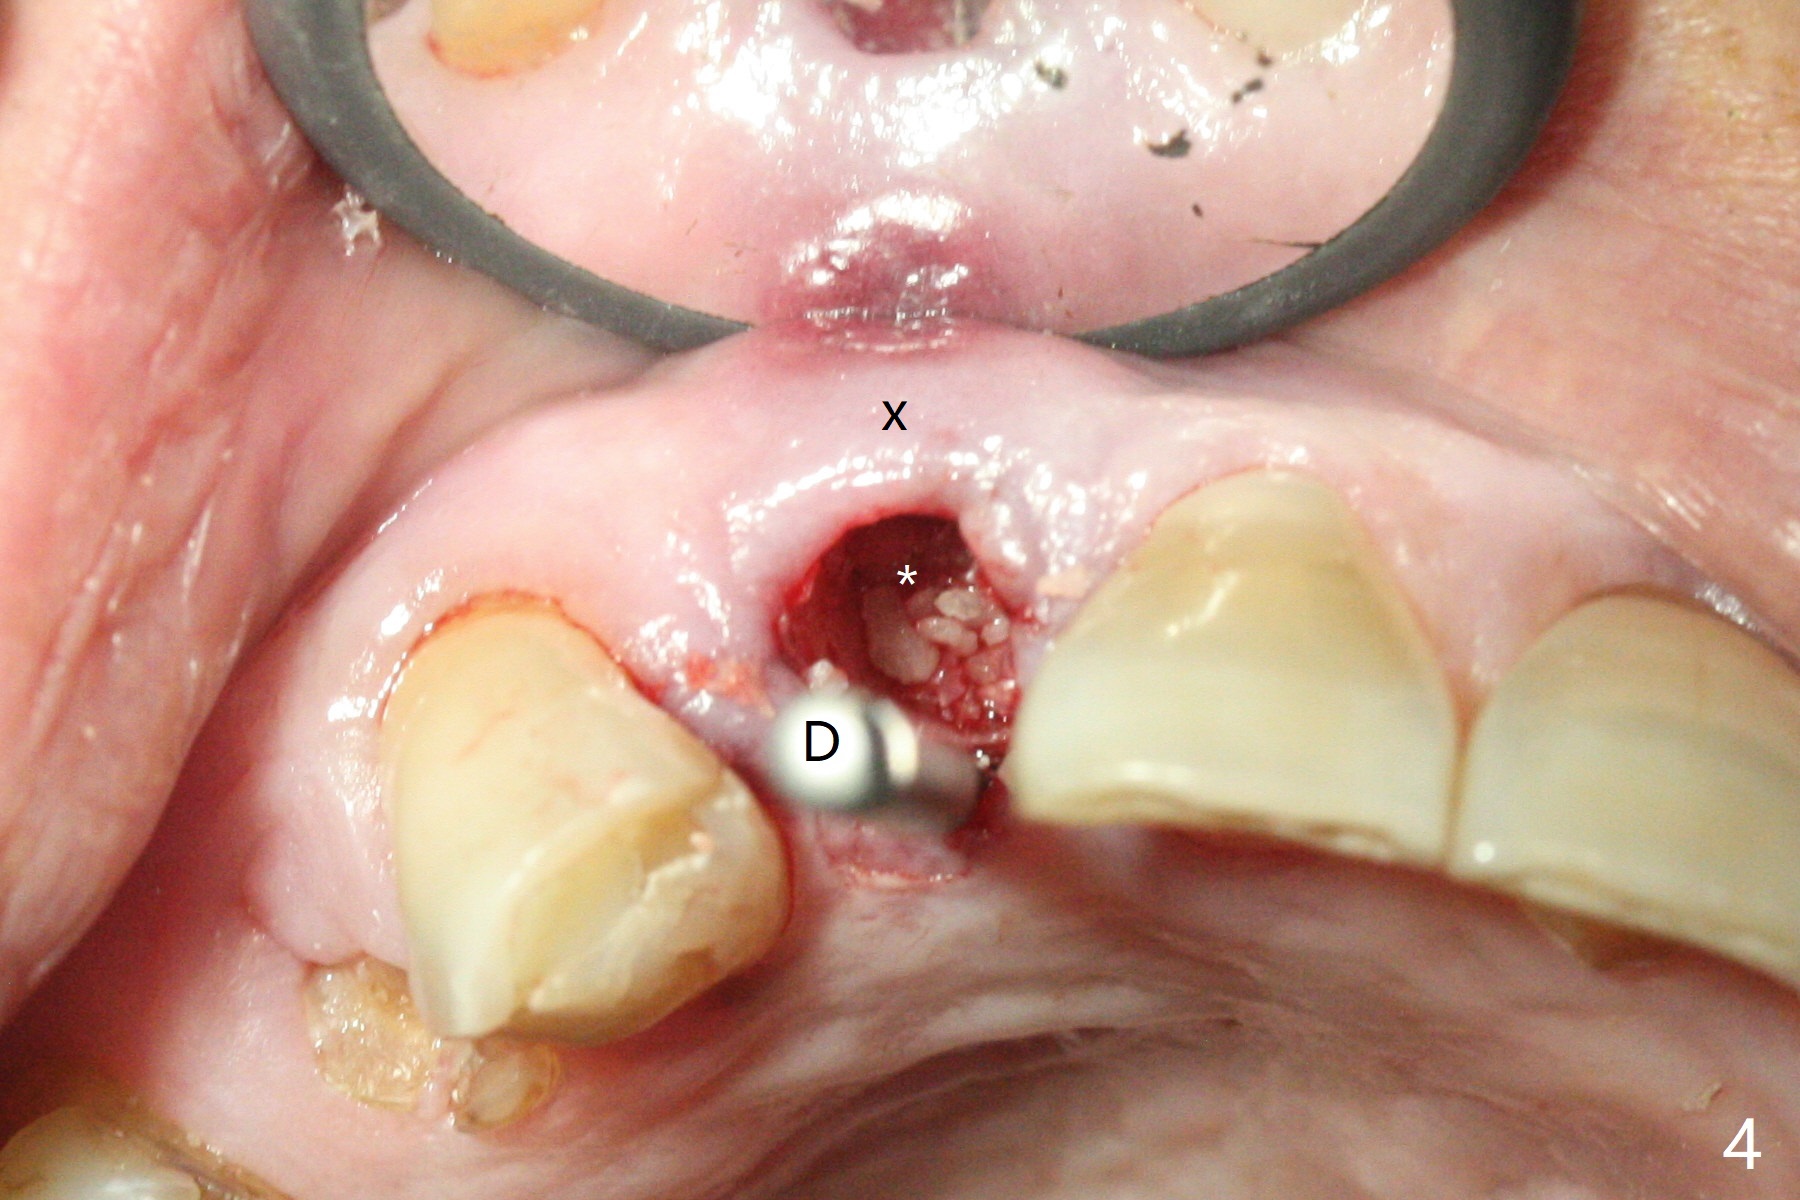

An apical abscess is present when the patient returns for immediate implant at #7 (Fig.1 *); a 2nd challenge is deep bite. After smooth extraction, the apical buccal plate is found to be perforated. Following debridement, a piece of gauze is placed in the apical defect for hemostasis, while osteotomy is initiated palatal (Fig.2). The apical defect seems to be extensive (Fig.3 yellow dashed line). A new trajectory is intended (red arrow) without much success. Before implant placement, bone graft is placed in the apical defect defect area, while a drill (Fig.4 D) is inserted in the finished osteotomy (Fig.5 O). In spite of seemingly large apical defect, the buccal crest bone exists (Fig.4 x). A 3x14(2) mm 1-piece implant is placed with stability; the first round of bone graft is apparently around the apical portion of the implant (Fig.6 *). The coronal end of the implant has to be adjusted several times buccopalatally to accommodate the deep bite. A 2nd round of bone graft following an immediate provisional closes the coronal space of the socket (Fig.7 *). CT will be taken to show the bone graft to repair the buccal plate defect when the patient returns for postop follow-up. In fact the defect is minimal in CT a month ago. The fistula does not disappear 1 week postop, but it is non tender (Fig.8). The patient complains of asymptomatic swelling in the right nostril. CT shows that the large buccal perforation is repaired with large amount of bone graft (Fig.9,10 *). It would be nicer to place the implant slightly more buccal apically (Fig.11 red lines; Fig.12 (preop design)). The buccoapical fistula disappears nearly 1 month postop (Fig.13). The apparently "lifeless" bone graft seems to be harmonious with the surrounding tissue (Fig.14). The periimplant gap reopens with implant mobility nearly 4 months postop (Fig.15), which is related to micro-movement associated with the immediate provisional. The latter is removed. A larger 2-piece implant will be placed in a 2-staged manner if needed (Fig.16). In fact the 3x14 mm straight 1-piece implant (Fig.17) has no mobility when it is retightened, but the trajectory remains buccal. Incision shows that there is no implant thread exposure. A 3x14 mm 15 degree angled 1-piece dummy implant is able to establish the correct trajectory, but there is no occlusal clearance (Fig.18). Micromovement during osteointegration may recreate loosening. Finally using Lindamann bur, the osteotomy is changed so that a 3.5x13 mm 2-piece implant does not need an angled abutment to establish occlusion (Fig.19). There is one palatal thread exposure. Allograft is placed circumferentially, followed by Human Amnion-Chorion Allograft and Collagen Plug. The wound does not heal 8 days postop (Fig.20), as related to the age (79 years old)? The wound appears to heal with a membrane on the surface (Amnion-Chorion one?) 3 weeks postop (Fig.21). The ridge looks wide 3.5 months postop (Fig.22,23). A 4.5x5.5(3) mm appears to be seated incompletely with a gap between the abutment and the implant (Fig.24<). A provisional is fabricated after heavy palatal reduction. Two months later, the provisional fractures. After repositioning the abutment with complete seating and torque (Fig.25), impression is taken. Although the buccal plate is concave, the gingiva remains healthy 10 months post cementation (Fig.26,27).